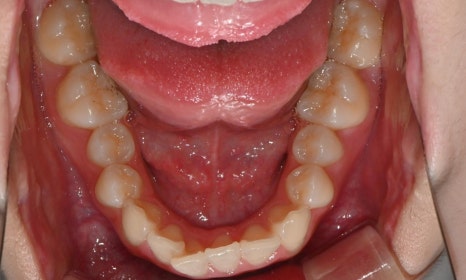

치료 후 전치부 배열이 정리되면서 웃을 때 스마일 라인도 한층 자연스럽게 개선되었습니다. 과개교합 역시 기능적으로 안정된 상태로 마무리할 수 있었습니다. 치료 후반부에 아주 경미한 중심선 차이가 남아 추가 장치를 통한 마무리를 권유드렸으나, 환자가 고2 학생으로 학업 일정이 바쁜 시기였고 현재 결과에 대해 본인과 보호자 모두 충분히 만족하여 이 상태에서 치료를 종료하기로 하였습니다.

치료 전후 스마일 라인 - 연세정원치과

무엇보다 이 환자는 8개월 동안의 치료 전반에 걸쳐 장치 착용을 매우 잘 지켜준 성실한 학생이었고, 그 결과 비교적 33단계의 효율적인 장치 갯수만으로도 안정적이고 만족스러운 결과를 얻을 수 있었습니다.

성장기 학생들의 교정 치료에서는 학업에 대한 부담, 외모 변화에 대한 걱정, 그리고 치료 기간이 중요한 고려 요소가 됩니다. 이번 케이스처럼 비교적 경미한 과개교합과 전치부 총생의 경우, 인비절라인은 일상생활과 학교생활에 큰 지장 없이 교정을 진행할 수 있는 좋은 방법이 될 수 있습니다. 또한 환자의 협조도가 좋은 경우, 비교적 효율적인 치료 계획으로도 안정적인 결과를 기대할 수 있습니다.